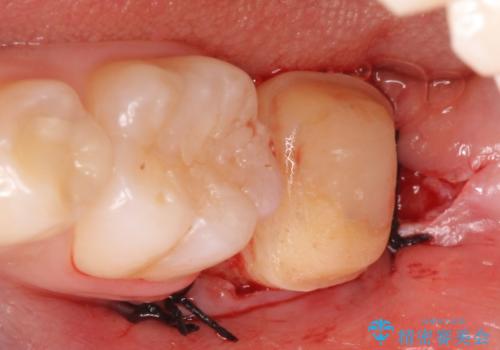

左下7遠心(下記のX線写真の左側)の歯質が歯肉縁下でかつポケットも深かったため、歯茎を下げる歯周外科を行いました。

そのため当院では歯周外科手術(歯茎を下げる手術)や歯の挺出による、虫歯が歯茎より深いという問題の解決を推奨しております。